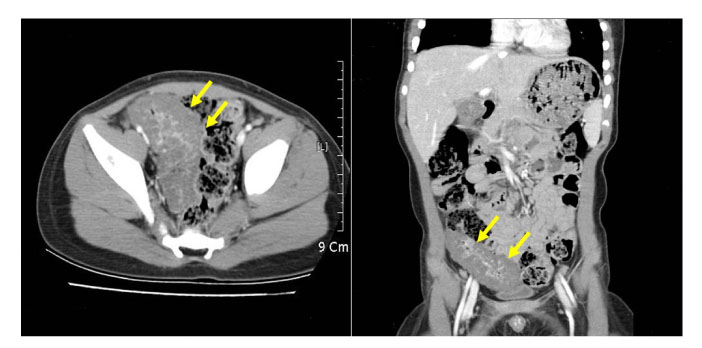

Fig. 2

Surgical specimen, showing a 10 × 4 cm circumferential blood-filled reddish mass involving the serosal surface of the jejunum.

Fig. 2 Surgical specimen, showing a 10 × 4 cm circumferential blood-filled reddish mass involving the serosal surface of the jejunum.